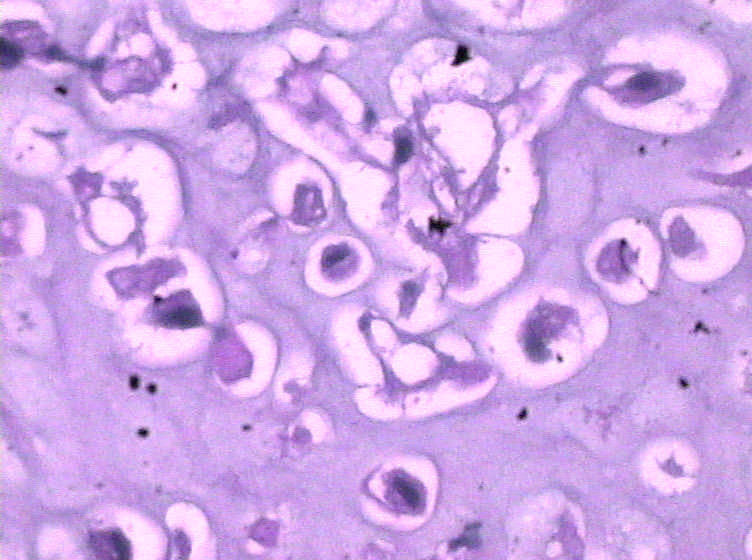

女,4岁,咽喉壁肿物。